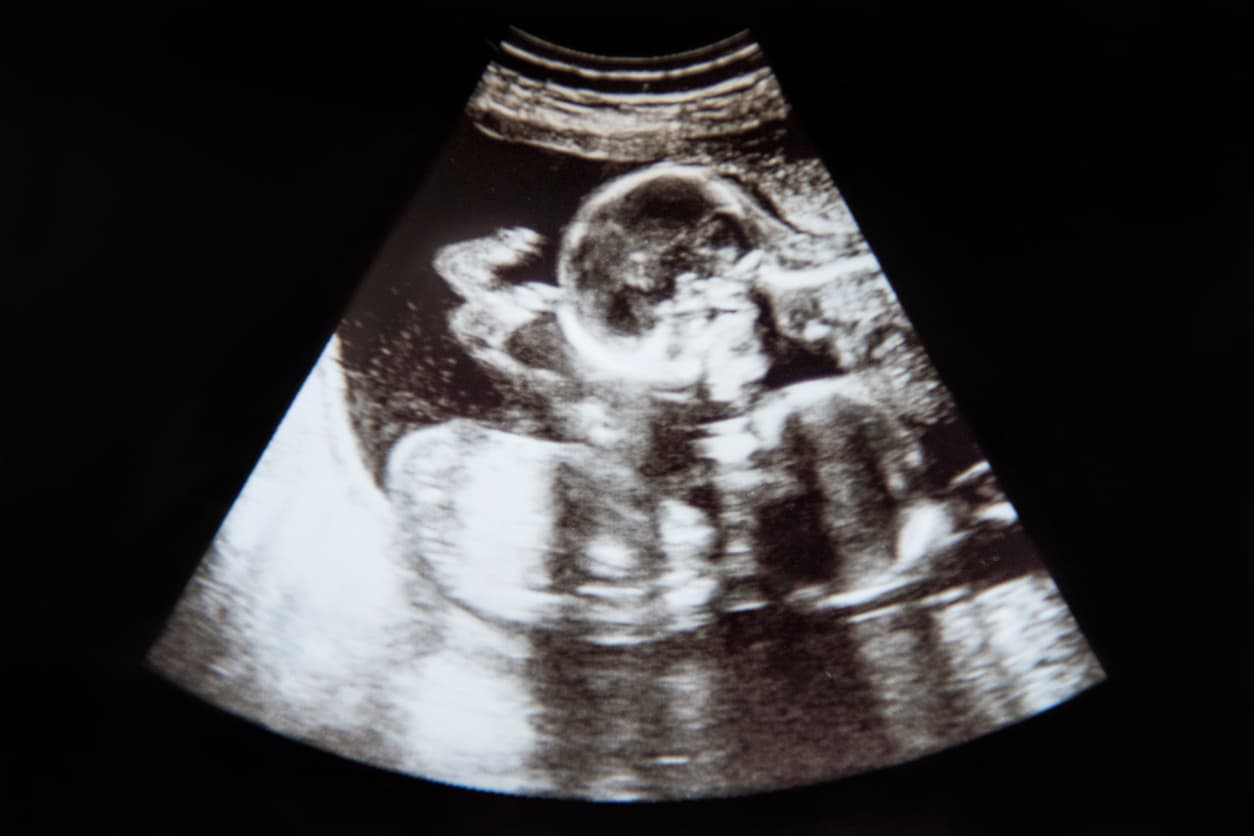

En esencia, dicha fertilización es la unión de un óvulo y un espermatozoide fuera del cuerpo y se realiza en un laboratorio de fecundación especializado para, después, transferir el o los embriones obtenidos en el interior del útero de la paciente.

Así que para tener gemelos con éxito mediante esta vía, se deberán transferir dos embriones. Si ambos se implantan y desarrollan, en 9 meses tendrás gemelos.